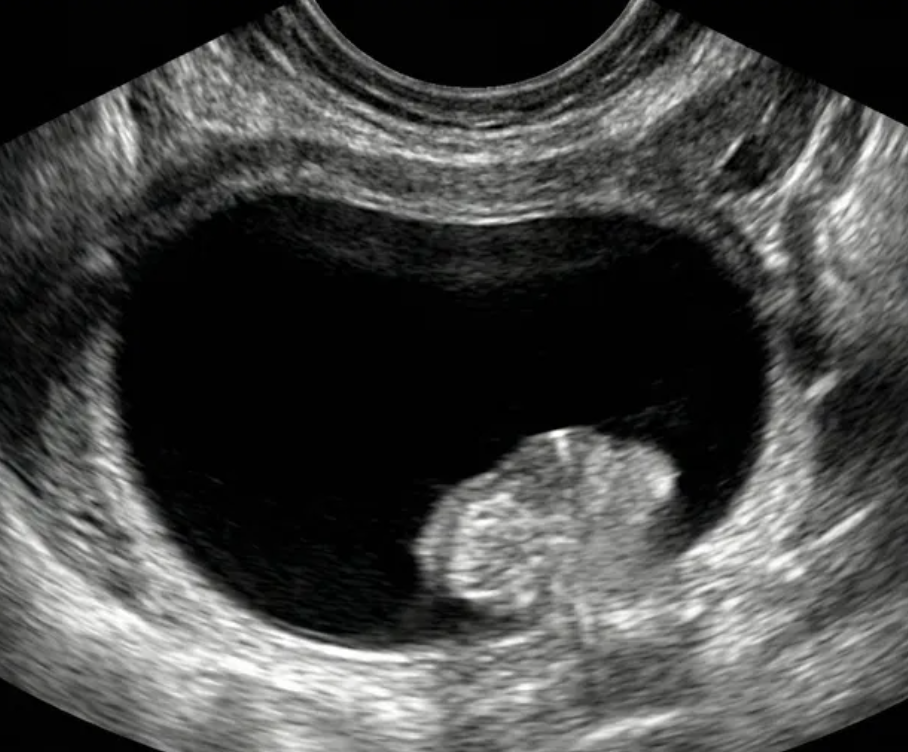

Risco: <1%Cistos simples, uniloculares lisos, lesões benignas clássicas (hemorrágico, dermoide, endometrioma, paraovariano, peritoneal, hidrossalpinge).

Achados ultrassonográficos (pré-menopausa)

Lesão benigna clássica